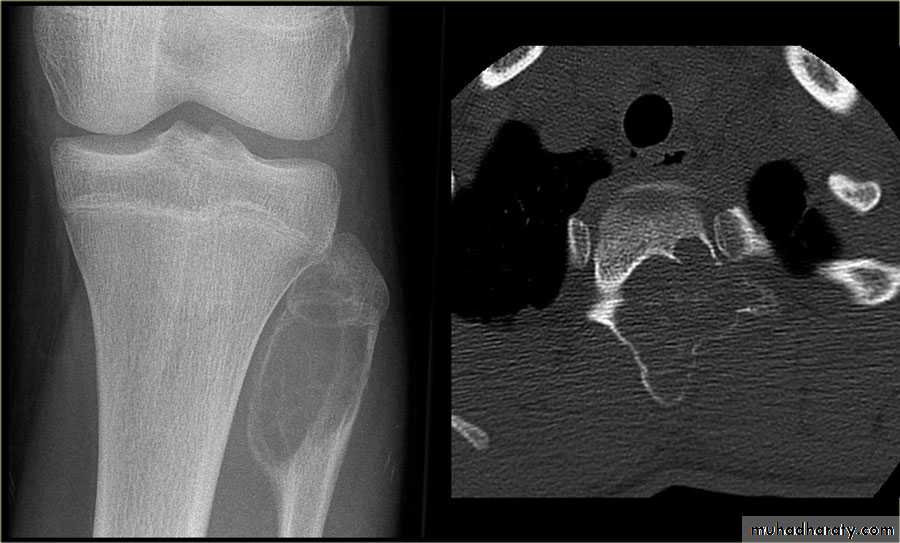

IV. computed tomography in bone disease (CT scan ) :

1.Demonestrating abnormality in the pelvis and spine2.Demonstrating the extent & characterization of bone tumour in selected cases to complement MRI

3.As gide of bone biopsy

the initial radiological decision is usually to try &decide whether the solitary lesion is benign or its aggressive by looking for the following features on plain radiographs & CT :

1.Zone of transition

2.The adjacent cortex

3.Expansion

5. Calcific densities within the lesion